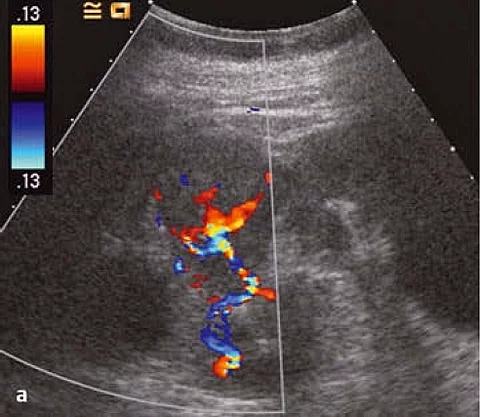

Differenzialdiagnostisch kann es sich um Metastasen der bekannten früheren Karzinome handeln, auch ein Onkozytom ist zu erwägen. Gegen ein Nierenzellkarzinom spricht das Fehlen von Tumornekrosen.